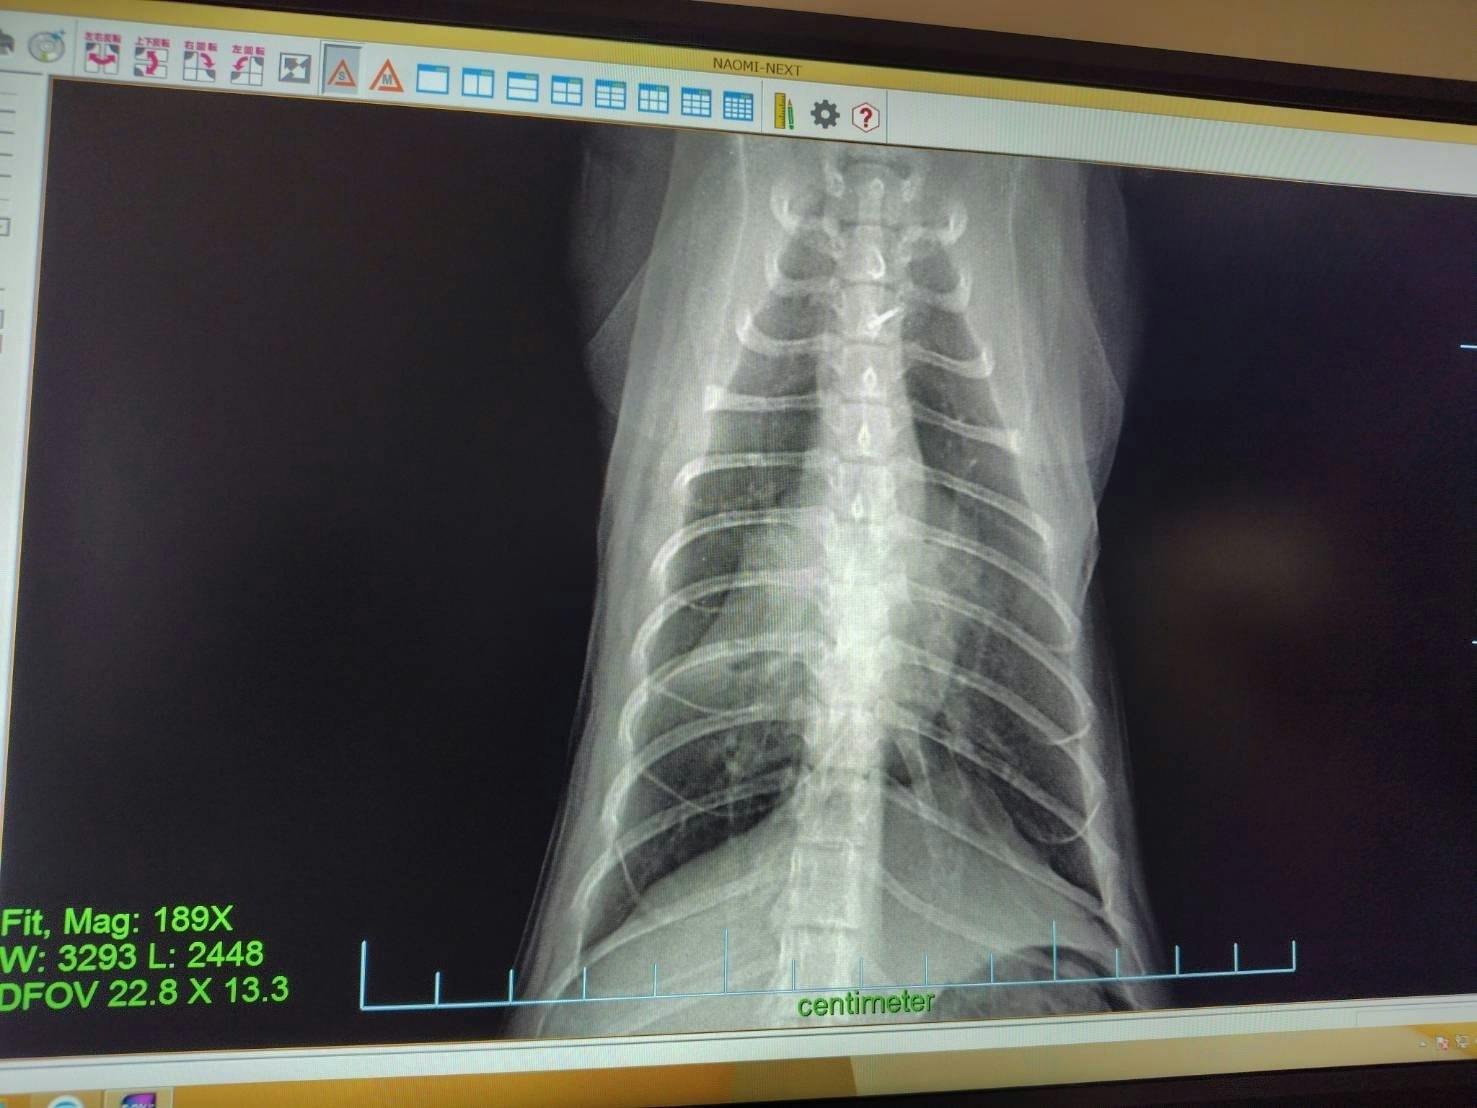

うちに来た時から変な咳をするので病院に連れて行ったところ、以前に風邪を拗らせて肺炎と気管支炎を併発しているとのことです。前にも同じことがありました。美観nekoのタプタプちゃんです。ブリーダーかペットショップで風邪をきちんと治してもらってなくて肺が心臓に癒着してました。風邪をひかないように気を付けておけば喘息も治るのですが、癒着はしたままになります。しっぽくも来た時からメヤニも多いし気にはなってました。これから定期的な治療に入ります。

抗生物質と喘息の治療です。